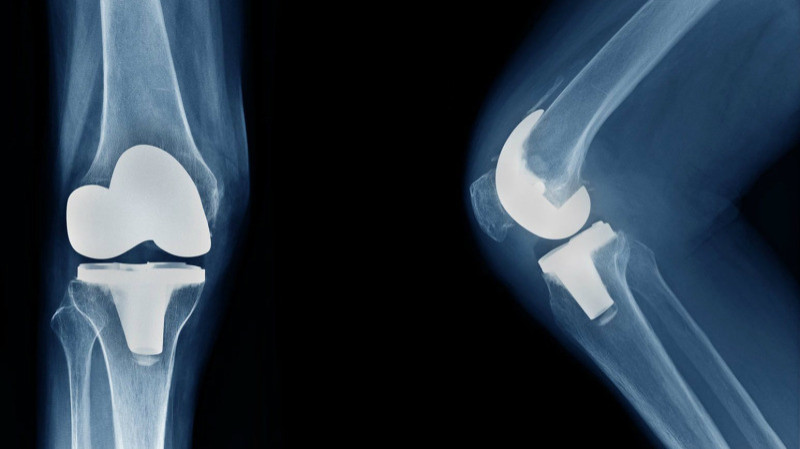

Knee replacement surgery aims to relieve pain, improve function, and restore mobility by replacing the damaged parts of the knee joint with artificial components made of metal alloys, high-grade plastics, and polymers.Best Knee Replacement Surgeon in Jagatpura, Jaipur It is generally considered when other less invasive treatments, such as medication, physical therapy, or less extensive surgeries, have not provided adequate relief.